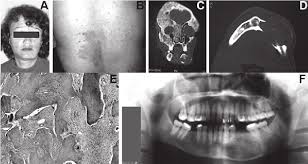

It is the only major dental journal that. Each chapter in GeneReviews is written by one or more experts on the specific condition or disease. OMIM174800 is a rare disorder characterized by skeletal lesions skin hyperpigmentation and hyper-functioning endocrinopathies 1 2It arises from post-zygotic gain-of-function mutations in the GNAS gene which encodes the α-subunit of the G s signalling protein These mutations disrupt the intrinsic GTPase.

Typically enchondroma is discovered on an X-ray scan. Oral Surgery Oral Medicine Oral Pathology and Oral Radiology Vol. It may predominantly affect the medullary portion andor cortex of bone. Each chapter in GeneReviews is written by one or more experts on the specific condition or disease. And The result of the test will directly impact the treatment being delivered to the member. OMIM174800 is a rare disorder characterized by skeletal lesions skin hyperpigmentation and hyper-functioning endocrinopathies 1 2It arises from post-zygotic gain-of-function mutations in the GNAS gene which encodes the α-subunit of the G s signalling protein These mutations disrupt the intrinsic GTPase. Cafè-au-lait skin pigmentations and endocrine dysfunction such as precocious puberty diabetes mellitus goiter and breast fibroadenomatosis 7 Radiographic features Typically seen as a well-circumscribed intramuscular mass. Oral Surgery Oral Medicine Oral Pathology Oral Radiology is required for all clinicians involved in the diagnosis and treatment of oral and maxillofacial disease. It is the only major dental journal that.

They have also been reported to cause increased uptake on PET examination. Can be associated with McCune-Albright syndrome endocrine abnormalities café au lait spots or Mazabraud syndrome soft tissue myxomas Transformation into sarcoma is extremely rare but has been reported typically decades after initial diagnosis J Formos Med Assoc 2004103711. This results from either increased proliferation or decreased apoptosis or both of developing neurons.